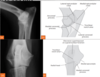

25

What is the periosteal reaction?

A bone change seen radiographically with neoplasias that can also be characterized into a type (4). - solid - onion peel or lamellated - spiculated - codman's